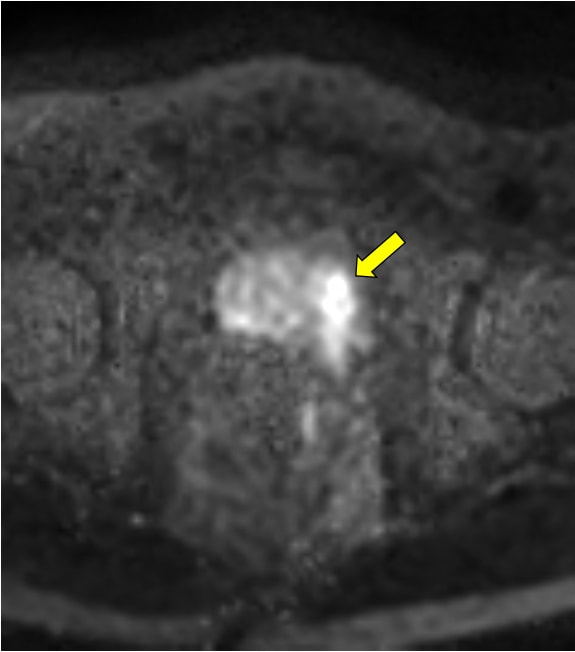

本症例ではPSA高値を契機に前立腺MRI検査を施行した。便秘症があるため、直腸は拡張し、内部にガスを含む便塊を認める。鎮痙薬は、既往症のため、使用せず、検査前の排便も不可能であったために、画質劣化が避けられない。腸管ガスによるひずみの影響で、全ての撮像シーケンスで、前立腺の後方の辺縁は不鮮明で、内部の信号が不均一となる。特に空気や蠕動の影響を受けやすい、拡散強調画像での画質劣化が著しい。

拡散強調画像(DWI)では、腸管ガスによるひずみの影響を減らすため、echo planar imaging(EPI)を用いたDWIよりTurbo spin echo(TSE)を用いたDWIを使用する。high b valueの画像は、computed DWIで作成することで、実際の撮像よりもノイズを低減できる場合がある。また、ダイナミック造影MRIを追加すると、短時間撮影のため前立腺の輪郭も明瞭で、癌部と非癌部のコントラストがつき、病変の検出に役立つ場合がある。